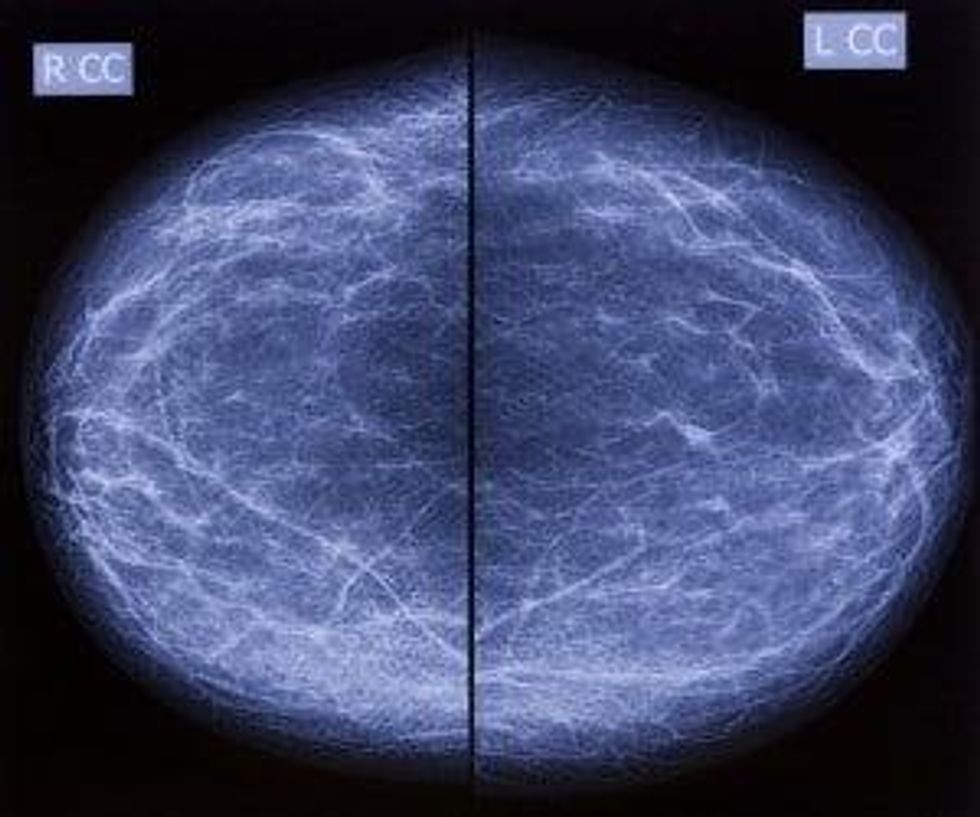

When breast tissue is dense, it appears white on a mammogram. Unfortunately, breast cancer also appears white, so in a traditional mammogram, trying to find a breast cancer can be like trying to isolate a snowflake in a snowstorm.

This is an image from a mammogram of a what very dense breast tissue looks like. Can you spot the breast cancer?

Increased breast density